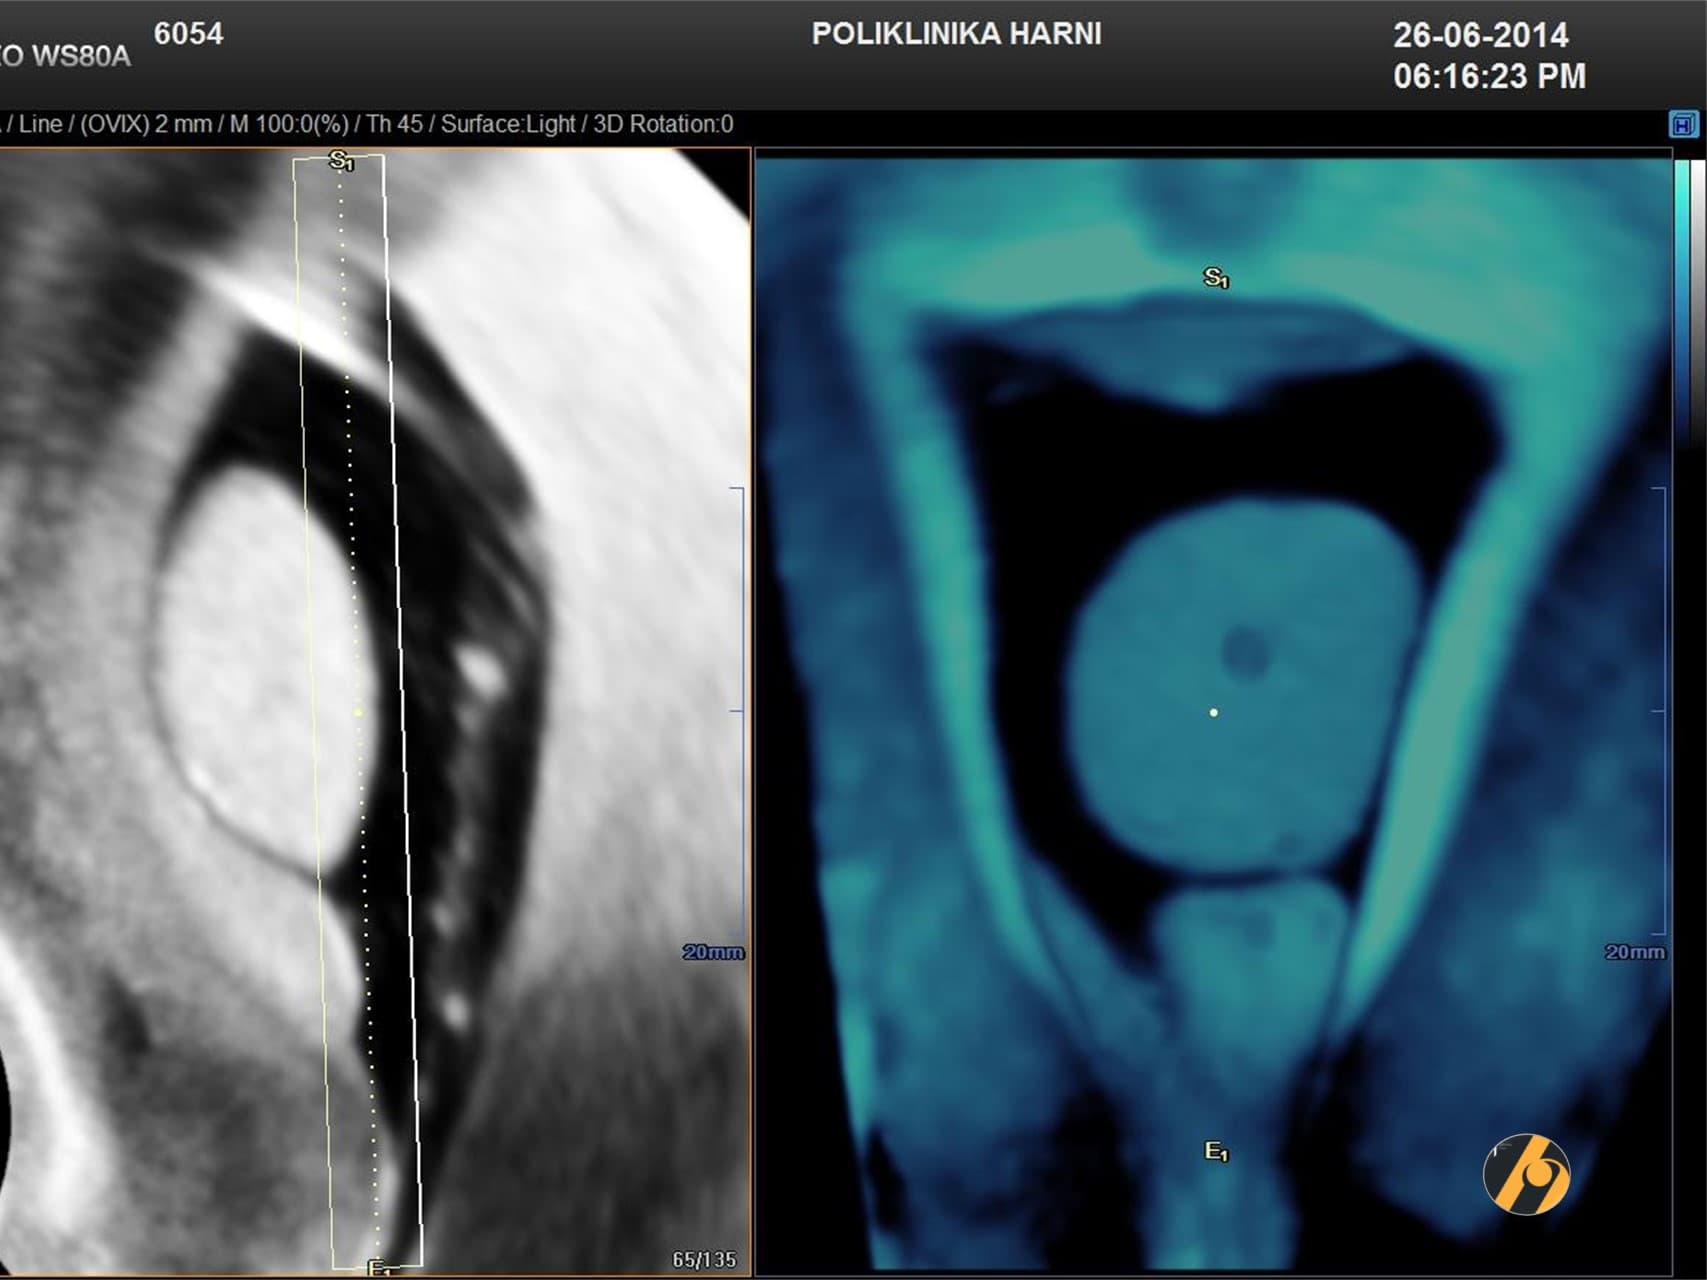

- 3D UZV (trodimenzionalni ultrazvuk) — uveden 1990-ih. Umesto klasične slike, analizira se volumen, koji se može rotirati i dodatno procesirati u različitim ravninama i modusima.

- 4D UZV (četverodimenzionalni ultrazvuk) — omogućuje praćenje 3D volumena u stvarnom vremenu, što je važno u funkcionalnim analizama i fetalnoj dijagnostici.

- 5D UZV (petodimenzionalni ultrazvuk) — označava dodanu automatizaciju i prikaz >12 presjeka iz jednog volumena, uz optimizirani softver i prikaz sličan CT-u. Koristi se i u folikulometriji, pregledu jajnika, fetalnoj neurosonografiji i ehokardiografiji. Ovi uređaji omogućuju i automatski prijenos UZV slika na mobilni uređaj pacijentice.

Pojava višedimenzionalnog ultrazvuka omogućuje prikaz ne samo određenih dijelova maternice koji nisu dostupni dvodimenzionalnom pregledu uslijed položaja uterusa, već i odabir optimalne ravnine kao i načina prikaza sumnjive lezije. Trodimenzionalni / 3D-UZV uveden je u uporabu devedestih godina 20. stoljeća. Po prvi puta u ginekologiji koristimo volumen, a ne sliku tako da je stvorena mogućnost prostornogf, volumetrijskog i višepresječnog prikaza. To znači, da uzeti volumen možemo dodatno obrađivati njegovim rotiranjem i stvaranjem presjeka u različitim ravninama i modusima. Praćenje trodimenzionalnog prikaza u stvarnom vremenu odlika je četverodimenzionalnog ultrazvuka / 4D-UZV.

Nove tehnološke opcije osigurale se automatske presjek koji omogućuju slojevitiju sliku, pa se automatski prikazuju 12 ili više presjeka po jednoj ravnini volumena, što poboljšava dijagnostičku točnost. Ovaj automatizirani ultrazvuk čije su slike osobito važne u fetalnoj neurosonografiji i ehokaradiografiji, ali i pregledu jajnika, pa i običnoj folikulometriji, nazvan je petodimenzionalnim ultrazvukom / 5D-UZV.

U ovim aparatima ugrađene su i opcije automatskog prijenosa ultrazvučnih slika na mobilni aparat pacijenta.. 5D ultrazvučna tehnologija označuje dodatnu, vrhunsku kvalitetu revolucionarnog ultrazvučnog sustava uz automatizaciju tehnike koja više nije apsolutno ovisna o ultrasoničaru, uz najveću kvalitetu dijagnostičkog prikaza na LED monitoru i optimiziranim softverom, koji omogućuje novu slojevitu, dubinsku sliku poput CT prikaza u stvarnoj trećoj dimenziji u svim otvorenim pitanjima kako u ginekologiji, tako i opstetriciji.